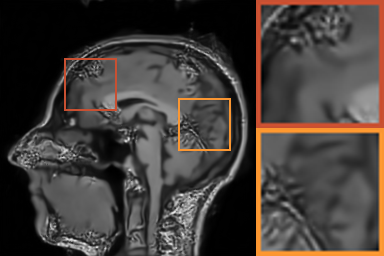

First, we test on 25 T1-weighted MRI data using three different undersampling patterns with a fixed 10% sampling rate. Fig. 3 shows the quantitative results (PSNR). Our method performances best for all three cases and has stronger stability compared with the second best method on variance. As for the effect of sampling ratios variation, we use radial mask under 10%, 30% and 50% sampling rates with evaluation of RLNE and MSE. Fig. 4 shows that our method has the lowest reconstruction error for all sampling rates. For more intuitive comparison, we illustrate the reconstruction error in term of pixels in Fig. 5. We also offer the qualitative comparison in Fig. 6. Visualized results demonstrate our method has better performance in both artifacts removing and details restoration. Time consuming is also considered. We compare our method with others on the 25 T1-weighted data using Radial mask with 10% and 50% sampling rate. Notice that ADMM-Net and ours are tested on GPU for the incorporation of deep architecture. Tab. 1 shows that our method provides an efficient reconstruction process and comes to the fastest method among the state-of-the-art competitors.

To demonstrate the robustness of our approach, we first apply it on various MRI data including the chest, cardiac and renal (?). In Tab. 2, Our proposed framework gives the highest PSNR for all of the tree types of MR images. Fig. 7 visualizes the corresponding results for chest data. we can see that our approach prevails over others in detail restoration at the junction of blood vessels as well as noise removal in the background. Actually, our method has a stronger ability to handle slight noise because of the subprocess of learning based optimization with deep prior. To demonstrate that, we add Rician noise at level of 20 to 25 T1-weighted MRI and 25 T2-weighted MRI to generate the noisy data. As what is shown in Fig. 8, our method over leads all the competitors by a large margin when the input is corrupted with Rician noise.